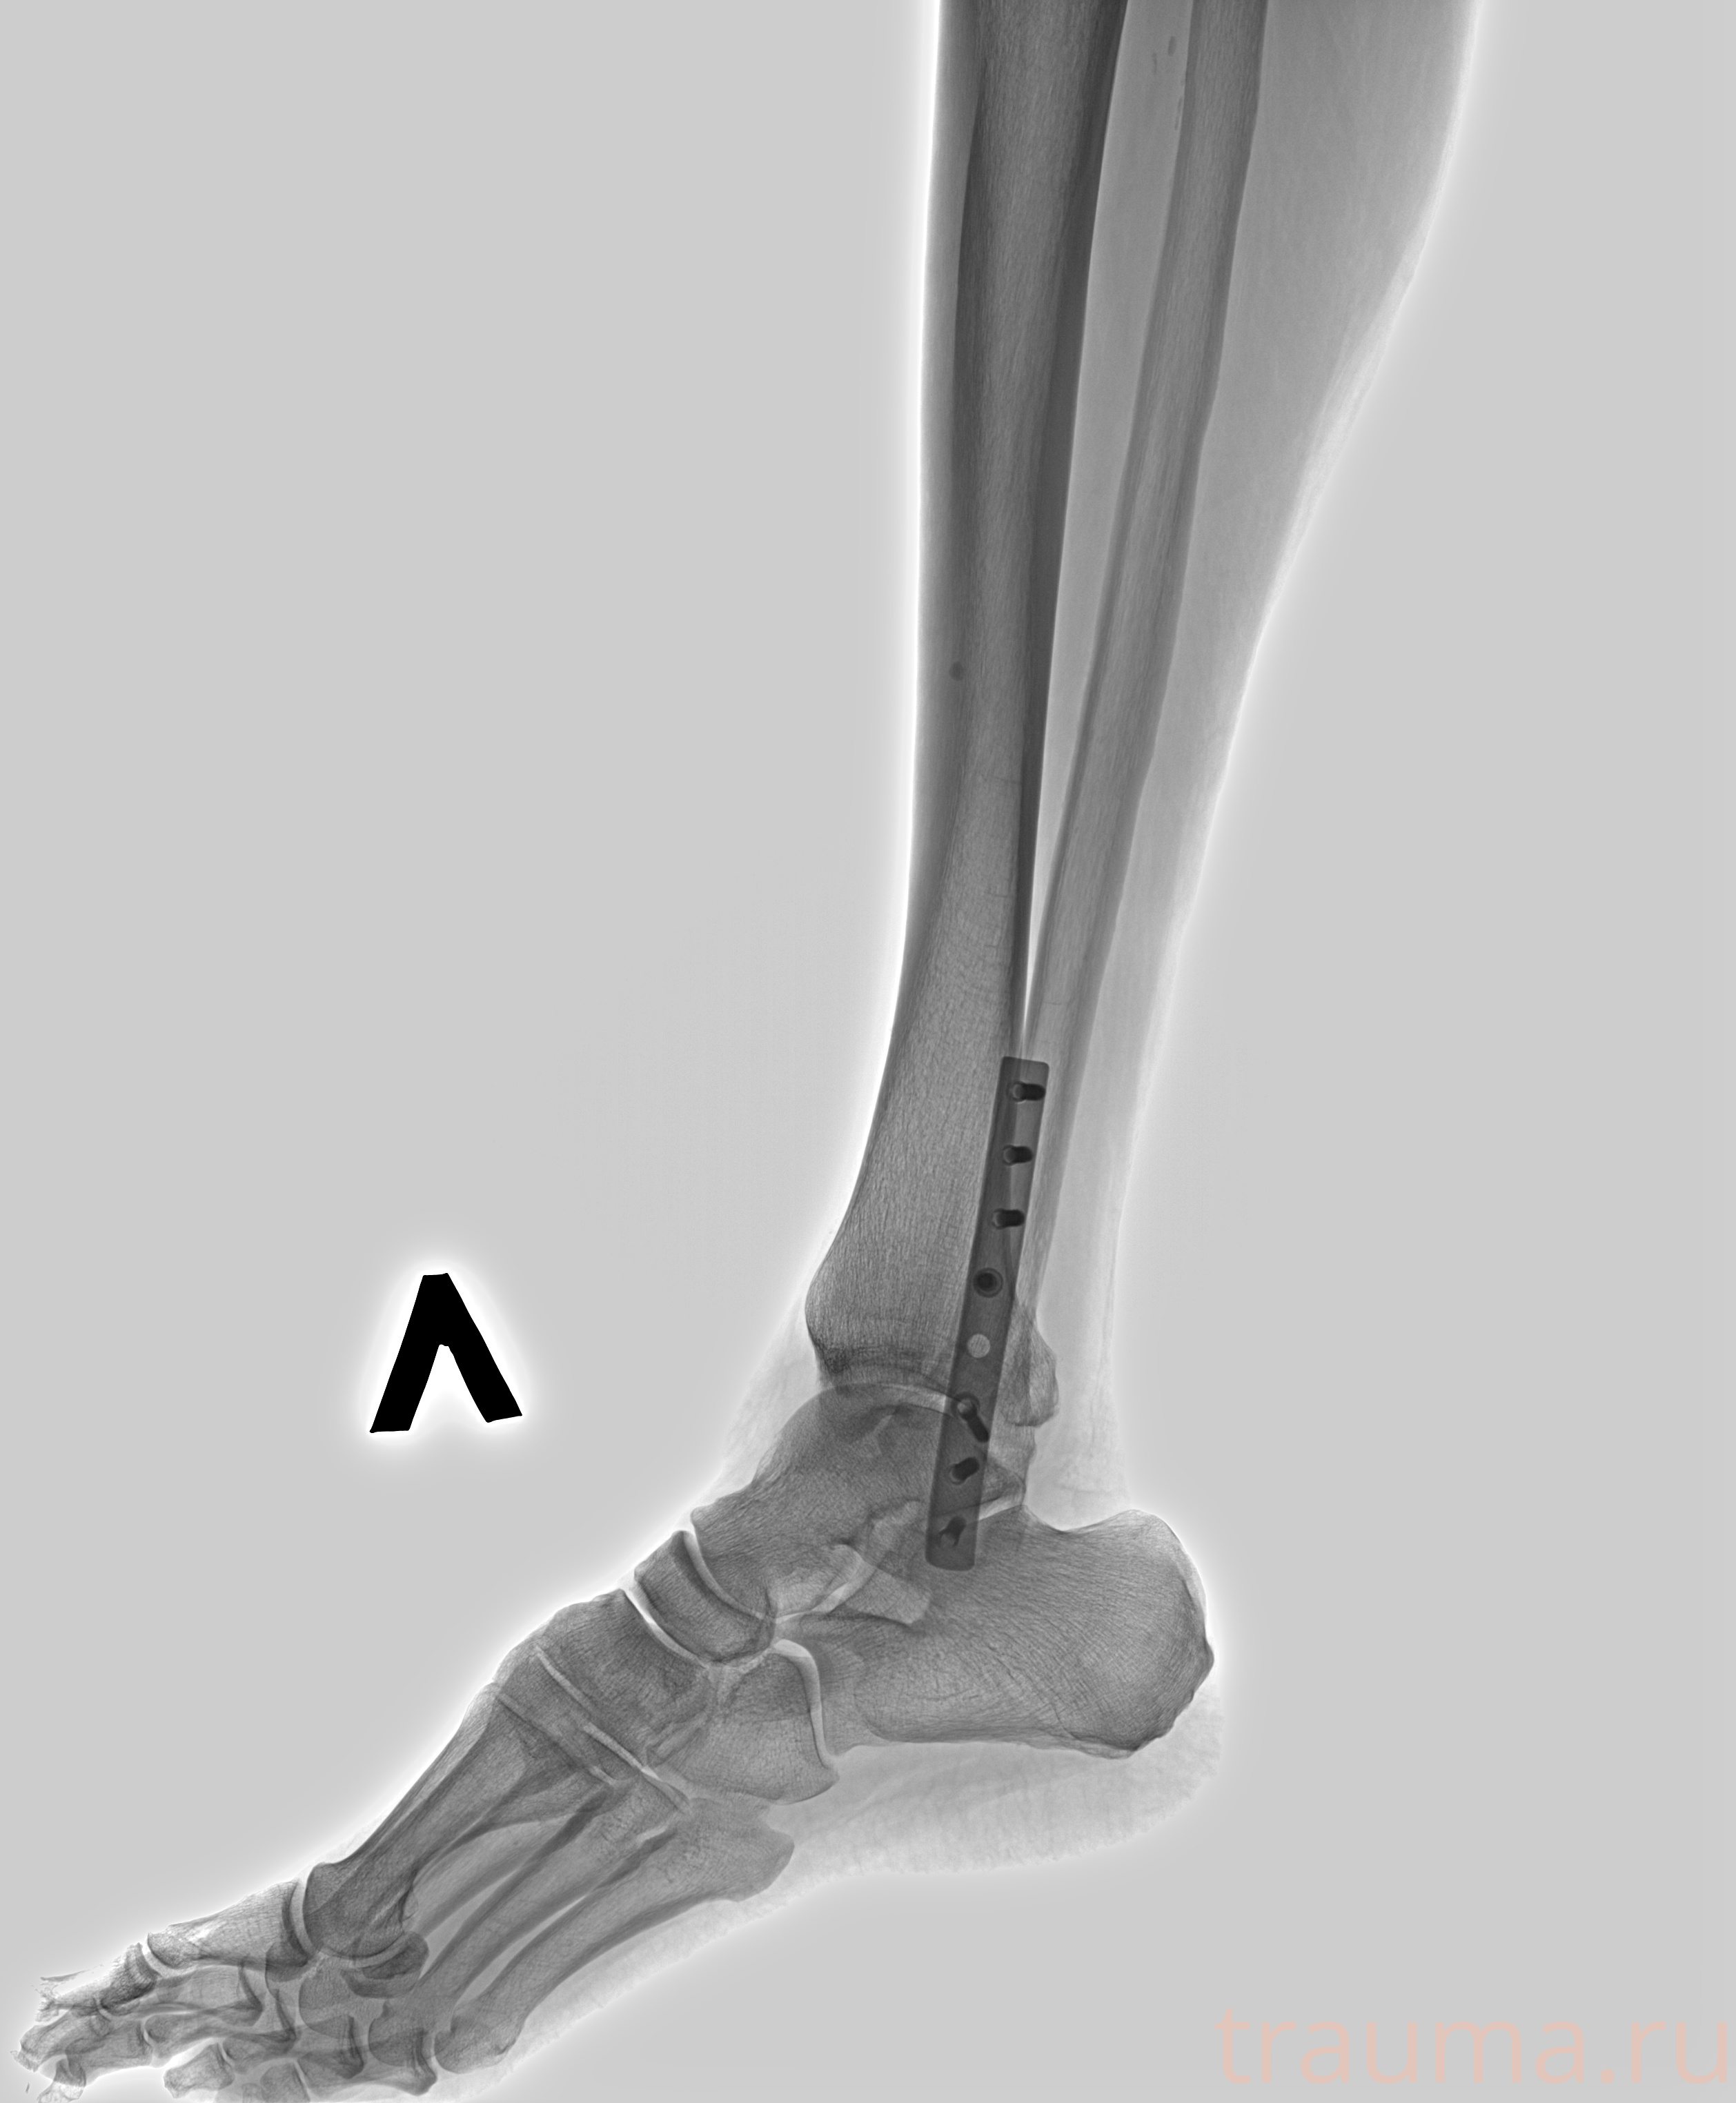

Рентгенограммы